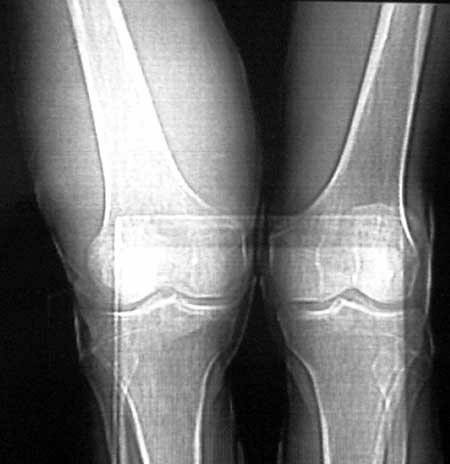

男56涨疼5-6月

右股骨下端包绕股骨见巨大软组织肿块,密度部俊,周围见瘤骨,下端骨皮质侵蚀变薄,骨质周围无骨膜反应, 考虑右股骨软骨肉瘤。

右股骨下段周围软组织肿块伴钙化,相邻股骨骨皮质受累,考虑软组织来源恶性病变

右股骨下段骨肉瘤,软组织内瘤骨,软组织肿块。